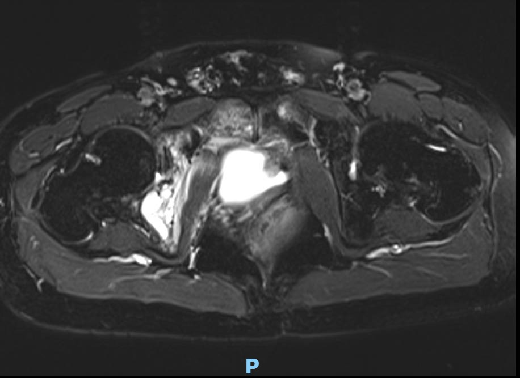

复查盆腔MR:

微信截图_20231221155956.png

前列腺癌术后复发,并侵犯膀胱左后壁。

双侧髋臼、坐骨、耻骨联合多发骨转移瘤。